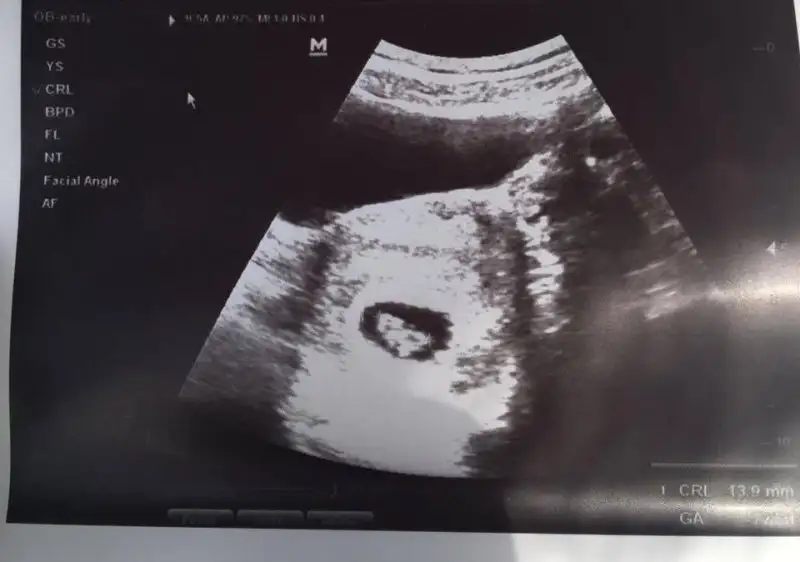

Kızlar merhaba benim bebişim için de cinsiyet tahmininde bulunabilir misiniz? Karından ultrason 6+1 ve 7+5 :)

• 6+1.webp

6+1.webp

13 KB · Görüntüleme: 217

• 7+5.webp

7+5.webp

14,1 KB · Görüntüleme: 249